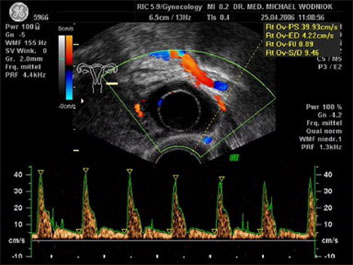

Hochauflösende Ultraschalluntersuchungen in Kombination mit der 3D-4D Technik werden in unserer Praxis routinemäßig durchgeführt. Dabei werden im Rahmen der Vorsorgeuntersuchung, sowie bei reinen vorsorglichen Ultraschalluntersuchungen auf Wunsch, auffällige Tastbefunde und noch unentdeckte Befunde weiter sonografisch abgeklärt. Bei zweifelhaften Befunden der Brüstdrüsen oder von Organen der inneren Genitalien kann der zusätzliche Einsatz der Farbdopplertechnik sehr hilfreich sein. Dabei stellt diese Technik bildlich sehr genau den Blutfluss, die Flussgeschwindigkeit, den Blutflusswiderstand sowie die Blutflussrichtung aller Blutgefässe dar. Die Interpretation dieser Ergebnisse fließt als zusätzlicher „Marker“ in die Entscheidung für das weitere klinische Vorgehen ein. Ein zunächst als völlig unauffällig eingestufter Ultraschallbefund eines zystischen Befundes im Eierstock wird bei einem unerwartet auffälligen Blutfluss an der inneren Zystenwand eine zeitnahe weitere Abklärung zu Folge haben. ![]() ![]() ![]()